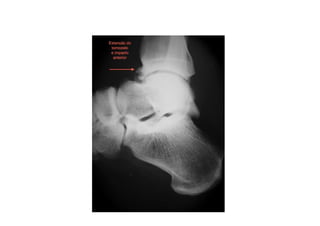

Síndrome do Impacto Anterior do Tornozelo

figura

• A região anterior do da tíbia forma osteófitos, que são bicos ou

proeminência ósseas. Da mesma forma temos a formação de osteófitos no

tálus o primeiro osso a se articular com a tíbia nos movimentos de flexão e

extensão do tornozelo.

• Uma das hipóteses da formação dos osteófitos seria uma flexão plantar do

tornozelo forçada, causando lesão da cápsula articular anterior e formação

de osso na região da lesão.

• Tais formações ósseas surgem nos tornozelos de praticantes de esportes

que realizam mudanças bruscas de direção.

• As radiografias demonstram uma formação óssea achatamento do bordo

anterior da tíbia e também no tálus

• Filmes realizados com o pé em dorsiflexão podem demonstrar o

contato dos osteófitos anteriores da tíbia com o tálus.